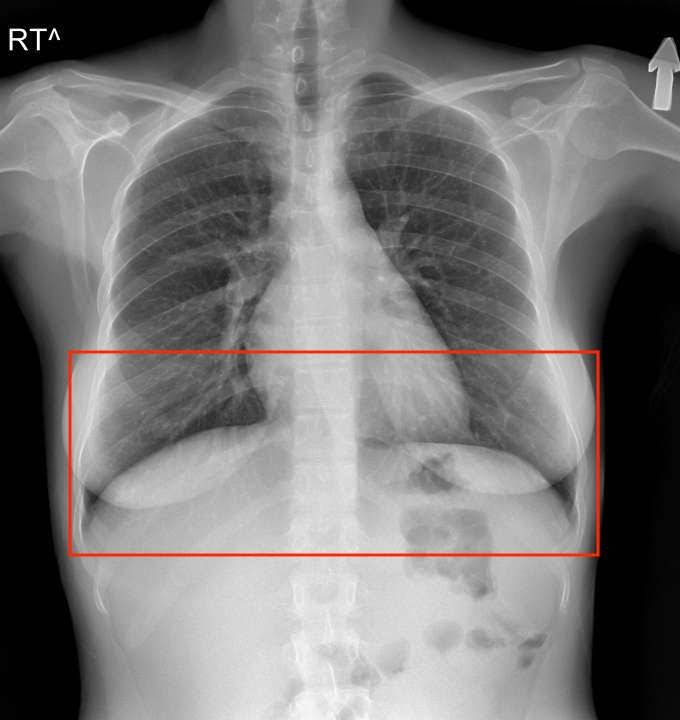

看看下面的胸部 X 光片,自己决定——肺是在横膈膜后面还是前面?

胸部 X 光片显示肺的下部,在横膈膜前面向后延伸,在横膈膜后面向前延伸

答案是……两者都有!传统的计算机视觉方法无法感知肺部被遮挡的部分;然而,深度神经网络可以很容易地学会发现它。